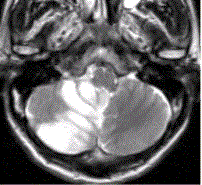

问题 患者女,75岁,突发偏瘫、头痛、头晕10h。既往有高血脂、糖尿病史。MRI表现如下图。 下述描述错误的是

选项 A.DWI显示异常的区域小于PWI显示异常的区域,可定义为缺血半暗带 B.DWI正常而PWI减低,提示为一过性脑缺血 C.MTT延长,CBF减低,CBV正常提示缺血前期微循环改变 D.MRS显示缺血区Lac/Cr升高,NAA/Cr降低 E.急性脑梗死区在DWI、ADC图上均呈高信号

答案 E